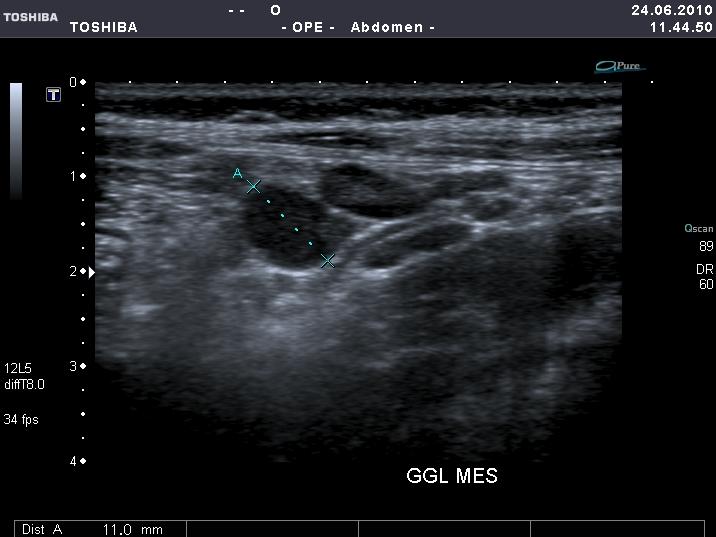

7 eves kislany diffuz hasi fajdalommal, minimalis nyomaserzekenyseggel a jobb alhasi regioban. A labor negativ.